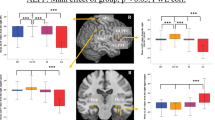

The ANOVA results showed significant dALFF variability differences across the three groups spread over eight clusters, including the right middle temporal pole (MTP)/superior temporal gyrus (STG), left middle temporal gyrus (MTG), left inferior frontal gyrus (IFG) extending to the left insula, left middle frontal gyrus (MFG), left superior frontal gyrus (SFG), right SFG, right supplementary motor area (SMA), and right insula extending to the right putamen (Fig. 1a).

a ANOVA results showing dALFF variability differences across three groups. b–c Post hoc results among the MDD-SA, MDD-NSA, and HC groups. IFG inferior frontal gyrus, INS insula, MFG middle frontal gyrus, SFG superior frontal gyrus, MTG middle temporal gyrus, PUT putamen, MTP middle temporal pole, STG, superior temporal gyrus, SMA supplementary motor area, L left, R right. dALFF dynamic amplitude of low-frequency fluctuations, MDD major depressive disorder, SA prior suicide attempt, NSA no prior suicide attempt, HC healthy control

The post hoc analysis revealed that both the MDD-SA and MDD-NSA groups showed elevated dALFF variability in the left MTG and reduced dALFF variability in the right insula, putamen, SMA and SFG relative to the HC group. In addition, the MDD-SA group exhibited higher dALFF variability in the left MTG and lower dALFF variability in the left IFG, MFG, SFG, right SMA, SMA/SFG and right insula extending to the putamen than the MDD-NSA group (Fig. 1b–c, Table 2).

Two-sample t-test revealed that the dALFF variability was higher in the left MFG (T = 2.36, uncorrected P = 0.026) and right SMA (T = 2.30, uncorrected P = 0.028) in the MDD-RSA group than in the MDD-SSA group; however, no cluster survived correction for multiple comparisons (Fig. 2).

dALFF variability difference between MDD-SSA and MDD-RSA in the a left middle frontal gyrus and b right supplementary motor area. * Uncorrected P < 0.05. dALFF dynamic amplitude of low-frequency fluctuations, MFG middle frontal gyrus, SMA supplementary motor area, L left, R right, MDD major depressive disorder, SSA single suicide attempt, RSA recurrent suicide attempts